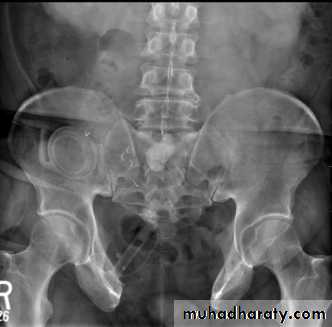

Ectopia vesica

(bladder extrophy) :bladder located at low position & plain x-ray shows separation of symphysis pubis .